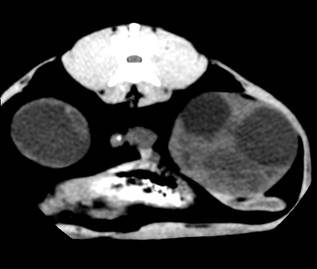

Комп’ютерна томографія нирок у домашніх собак

і кішок,

хворих на полікистоз. Враховуючи той факт, що в

доступній спеціальній літературі не вдалося знайти повідомлень щодо

застосування методу комп’ютерної томографії для діагностики ренальних патологій

у кішок, ми у своїй роботі вважали актуальним вивчення цього питання.

Комп’ютерну томографію застосовували, попередньо

встановивши діагноз з використанням загальних методів, ультрасонографії та

лабораторних досліджень. Дослідження здійснювали за допомогою покрокового

комп’ютерного томографу фірми «Siemens»

Somaton CR-X.

Тварин розміщували на рухомому столі приладу у спинно-черевному положенні, так

щоб під час процедури напрямок руху був краніо-каудальним. Забезпечували

належну фіксацію пацієнта. Томографію проводили при параметрах приладу 120 кV,

80mА у аксіальній

проекції. Визначивши краніальний полюс правої нирки, розпочинали сканування з

інтервалом 3-5 мм, аж до каудального полюсу лівої нирки. Результати аналізували

за допомогою комп’ютера та графічно.

За отриманими даними, полікистозні ураження обох

органів візуалізувались на томограмі у вигляді округлих утворень різної

щільності за шкалою Хаунсфілда, що певною мірою залежить від характеру вмісту

кіст (мал). Так, відносна гіподенсність (10-20 HU)

порожнини кіст може свідчити про низький вміст органічних речовин, що в свою

чергу можна характеризувати як неускладнений перебіг полікистозу. Більш висока

інтенсивність сигналу (50-60 HU)

свідчить про крововилив у кісту. Зростання інтенсивності сигналу у цьому разі,

очевидно, спричинене високим вмістом заліза у гемоглобіні, що й зумовлює зміни

парамагнітних властивостей середовища.

Рис.6. Серія КТ

сканів нирок кота. Кисти нирок, більше зліва